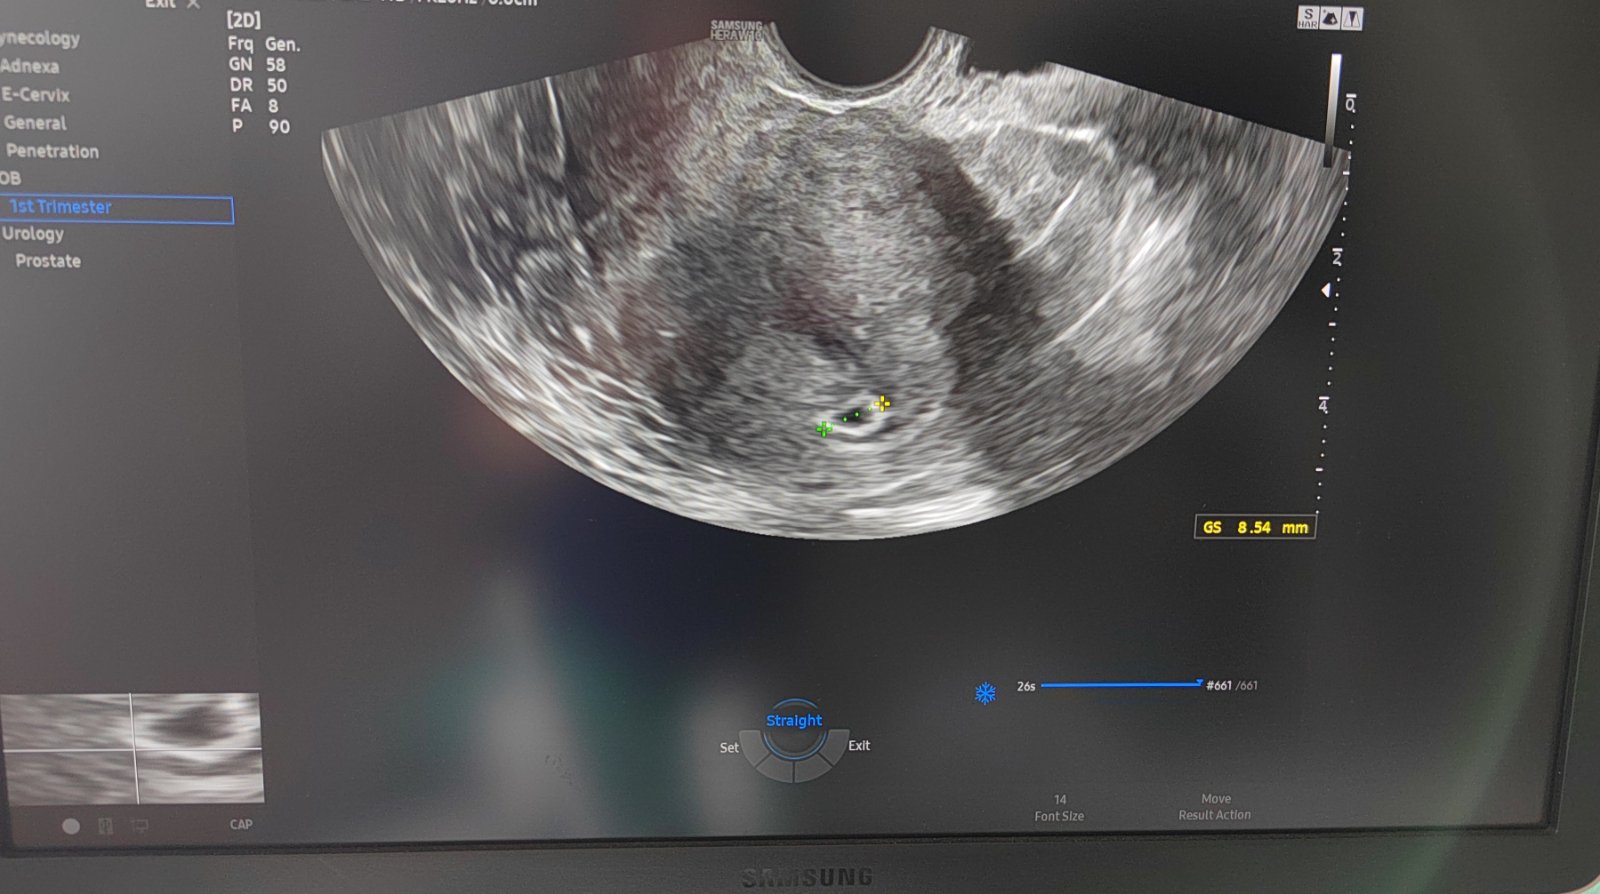

Nie je vidieť nič na sone v 6. týždni tehotenstva?

@sofia1979 no akurát som prišla od lekára, a nevyzerá to dobre, videla tam len takú malú kavitu, takže mi znova brali krv na hcg, zajtra mam volať za výsledok a vo štvrtok sa mám prísť znova ukázať, zatiaľ nevidela ani nič vo vajcovode a vaječníku, ale ešte stále nevylúčila mimomaternicové tehotenstvo, ale neviem prečo mám strašne zlý pocit, že to bude predsa len mimomaternicove. Ak hej prídem aj o druhý vajcovod 😔